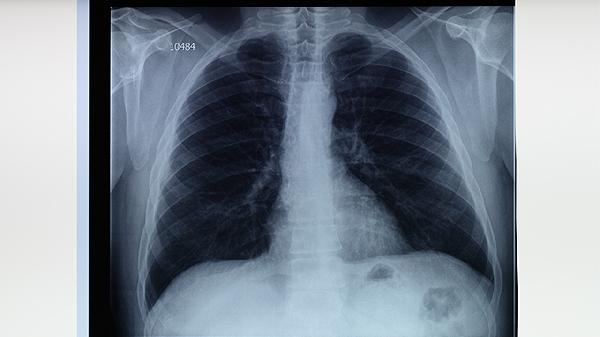

5.早期发现和治疗肺结核患者是阻断传播的关键。肺结核患者在未接受治疗前具有较高的传染性,及时诊断和规范治疗可以显著降低传播风险。建议有咳嗽、发热、盗汗等症状持续两周以上的人群及时就医,确诊后严格遵循医嘱服药,避免中断治疗。